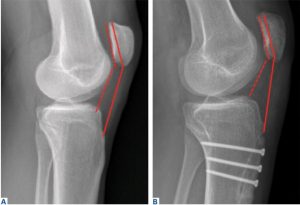

Οι δείκτες Insall-Salvati index και Caton-Deschamps index

i) αλλά και κλινικά τεστ λιγότερο όμως αξιόπιστα. Ακτινολογικά η ακτινογραφία προτιμάται να είναι σε μικρή κάμψη περίπου 10-20ο. Χρησιμοποιείται η μέτρηση μήκους επιγονατίδας και επιγονατιδικού τένοντα (insall-salvati index) ή η μέτρηση του μήκους της αρθρική επιφάνειας της επιγονατίδας από την κνήμη (Caton-Deschamps index). Ωστόσο όμως επειδή οι μέθοδοι αυτές είναι έμμεσες, ως προς την άρθρωση επιγονατίδας με το μηρό, έχουν το μειονέκτημα να μην περιγράφουν την πραγματική επαφή χόνδρων, αλλά σε ανατομικές διαφορές θα υπάρχει σφάλμα στη μέτρηση. Για το λόγο αυτό προτιμάται η μαγνητική τομογραφία και η μετρ

Patellotrochlear index

ηση του επιγονατιδοτροχιλιακόυ δείκτη (Patellotrochlear index) όπου φαίνεται η πραγματική επαφή χόνδρων.